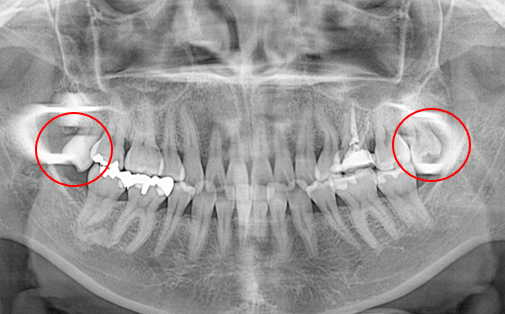

Before

After

左下の親知らずの歯を移植の症例です。